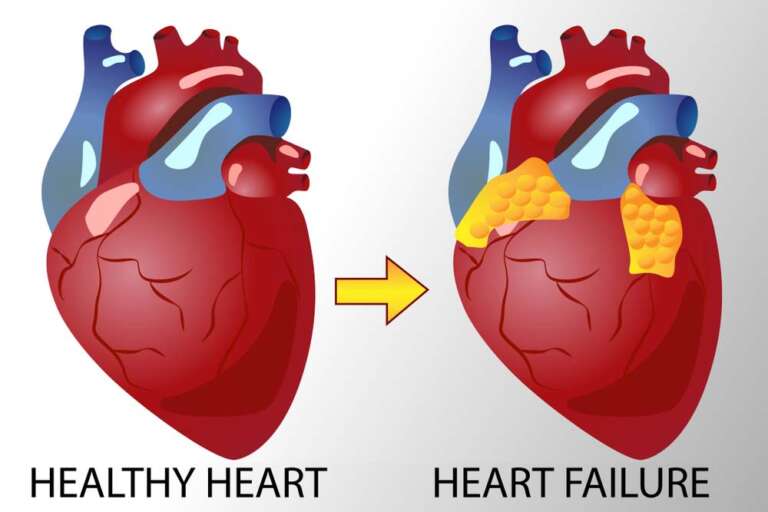

هل عملية قسطرة القلب خطيرة؟ مخاطر قسطرة القلب (القسطرة القلبية) تتضمن العديد من الأمور التي يجب أخذها بالحسبان قبل الخضوع للعملية ولكن عادة ما يكون خطر حدوث مضاعفات كبيرة أثناء إجراء قسطرة القلب التشخيصية أقل من 1٪ ومخاطر الوفاة بنسبة…